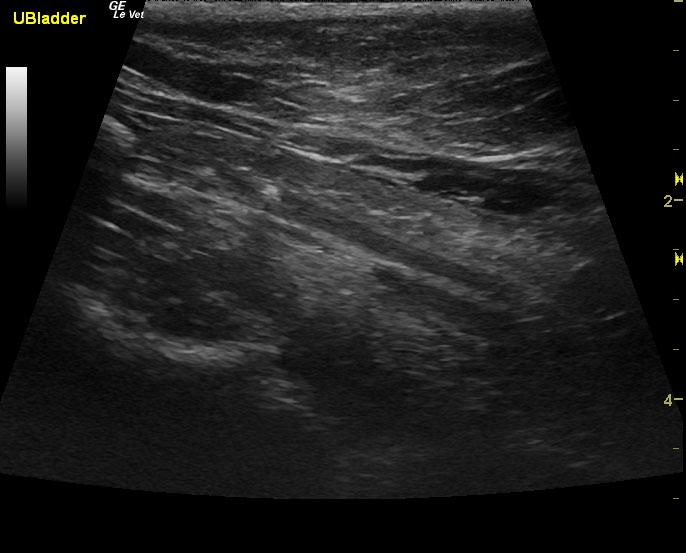

A 7-year-old FS DSH was presented for evaluation of recurrent hematuria and stranguria. Urinalysis showed protein and blood and a normal specific gravity. Culture was negative.

A 7-year-old FS DSH was presented for evaluation of recurrent hematuria and stranguria. Urinalysis showed protein and blood and a normal specific gravity. Culture was negative.